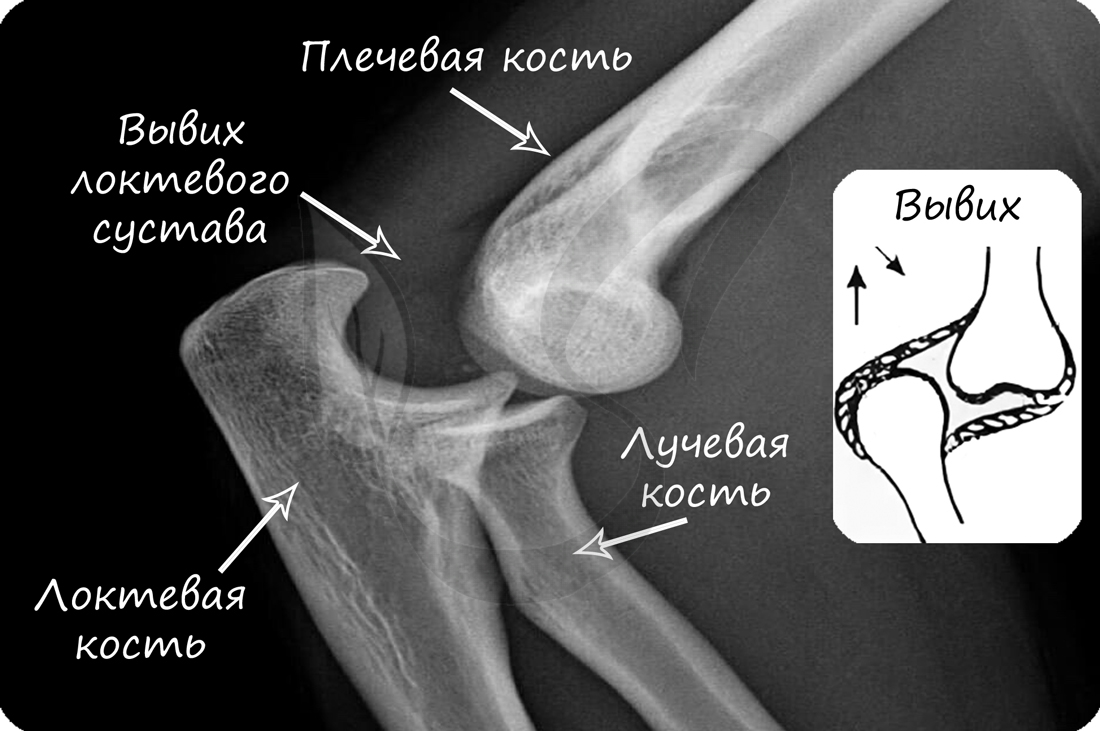

В норме кости могут смещаться относительно друг друга в суставе, однако при травме, слишком резком и сильном движении это смещение может быть слишком сильным: в результате нарушается соприкосновение суставных поверхностей. В таком случае говорят о возникновении вывиха.

Техника оказания медицинской помощи при вывихах:

Перед вправлением вывиха следует делать рентгенологическое исследование, чтобы убедиться в отсутствии переломов костей, которые иногда сопутствуют вывиху.